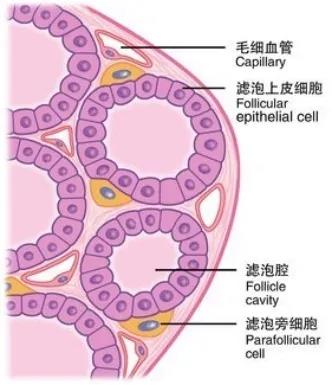

甲状腺是人体中非常重要的内分泌器官,外形像一只美丽的蝴蝶,通过分泌甲状腺激素促进物质和能量的代谢,对人体的多系统具有重要影响。近年来,随着人们体检意识的增强和超声诊疗技术的迅猛发展,甲状腺恶性结节的检出率呈逐年增高的趋势,而一旦确诊,颈部这只美丽的蝴蝶就面临着折翼的风险——外科手术切除。腺体切除、颈前瘢痕、终身服药像一幕幕阴霾,笼罩在患者的头上。 患者小Y是一个23岁年轻美丽的女孩儿,在哈医大一院超声医学科进行超声检查后,发现右侧叶有一枚大小约0.8cmx0.6cmx0.8cm的TI-RADS 4c类结节(图1),并且经过穿刺病理证实为甲状腺乳头状癌。这如同一个晴天霹雳般的坏消息,让这个女孩儿痛苦不已。如果选择手术切除,术后颈部的瘢痕、终身服药的不便、尚未结婚怀孕的现实难题,让小Y难以接受传统手术疗法。在了解到她的困扰后,哈医大一院超声医学科介入团队迅速启动科内会诊及病例讨论机制,在学科主任吴长君教授的提议下,决定采用超声引导下的射频消融治疗,对小Y的恶性结节进行局部灭活,并且尽可能保留正常腺体。通过术前审慎评估,细致准备,消融手术由超声医学科王俊峰副教授主刀。在实时超声的引导下,射频消融针精准的进入恶性病灶内,仅用时3分钟左右,消融范围就完全覆盖病灶(图2)。 治疗过程中,超声介入团队配合默契,采用多种技术保障患者安全,避免了甲状腺周围重要组织(血管、神经)的损伤。治疗取得了圆满成功。术后,小Y开心的笑了,超声介入团队也由衷的为她感到高兴(图3)。 哈医大一院超声医学科主任、博士生导师吴长君教授介绍,超声引导下射频消融治疗甲状腺乳头状癌,具有非常多的优点。在保障治疗效果的同时,可以满足患者个性化的需求。射频消融用时短,术后恢复快,无需终身服药,并且避免了颈部瘢痕,尤其对于爱美女性及拒绝终身服药的患者非常友好,是一种值得大力推广和应用的治疗技术。哈医大一院超声医学科介入团队秉承不断进取、精益求精的理念,着力打造甲状腺疾病诊疗一体化平台,为守护龙江人民的健康不懈努力!